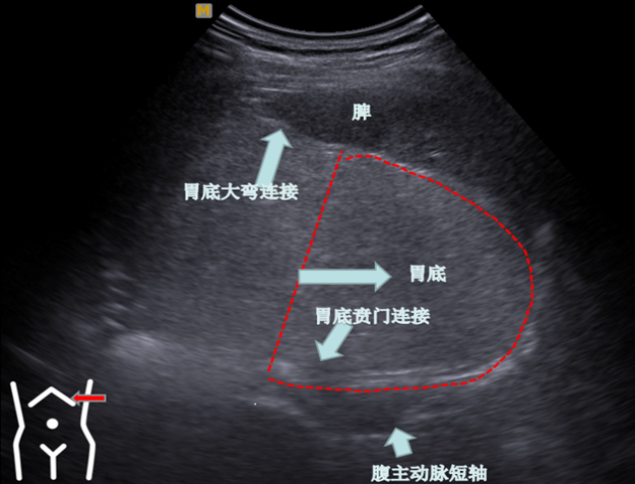

第二组胃底切面

受检者平卧或稍左卧位我们先在左肋间寻找脾以脾作为寻找胃底部界面胃底部区分是以贲门口为界限贲门以下部位就是胃底该切面为一倒C状近场与胃大弯连接远场与贲门连接在胃底切面也可以看到贲门因此我们称之为主看胃底附看贲门

受检者右卧位我们降探头置放左肋下朝左侧上翘以脾下缘作为寻找胃底短轴界面。